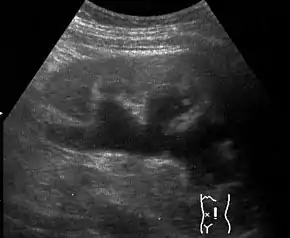

Renal ultrasonography of hydronephrosis caused by a left ureteral stone.

Imaging studies, such as an intravenous urogram (IVU), renal ultrasonography, CT, or MRI, are also important investigations in determining the presence and/ or cause of hydronephrosis. Whilst ultrasound allows for visualisation of the ureters and kidneys (and determine the presence of hydronephrosis and / or hydroureter), an IVU is useful for assessing the anatomical location of the obstruction. Antegrade or retrograde pyelography will show similar findings to an IVU but offer a therapeutic option as well. Real-time ultrasounds and Doppler ultrasound tests in association with vascular resistance testing helps determine how a given obstruction is effecting urinary functionality in hydronephrotic patients.[11]